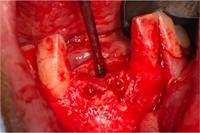

1. Before treatment